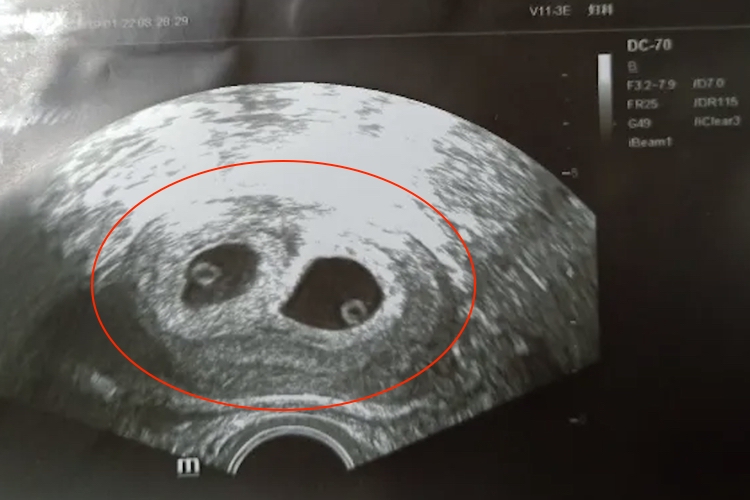

孕囊旁积液是相对复杂问题,可能涉及多种原因,包括正常生理现象、子宫内膜炎、先兆流产等,应及时就医并接受专业医生的诊断和治疗。

- 孕囊旁积液是先兆流产的常见表现之一,可能还伴有腹痛、阴道流血等症状。需要及时到医院进行B超检查,了解胎心胎芽是否有搏动。如果有搏动的情况,可以遵循医生指导给予保胎药物进行治疗,如果保胎失败或胚胎停止发育,则需要考虑终止妊娠。